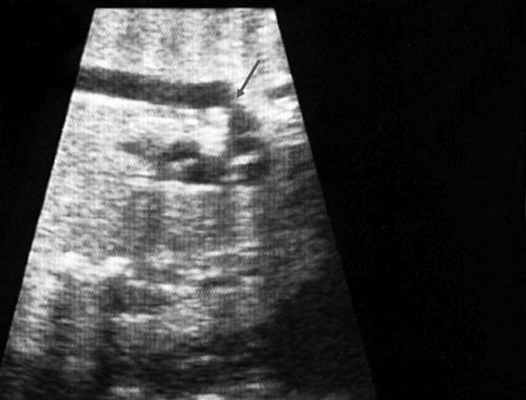

ЭХОКГ грудного ребенка. Дуга аорты. Незначительное сужение перешейка дуги аорты (отмечено стрелкой) – частая, клинически не проявляющаяся находка.